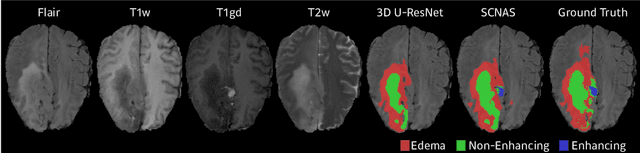

Abstract:In this paper, a neural architecture search (NAS) framework is proposed for 3D medical image segmentation, to automatically optimize a neural architecture from a large design space. Our NAS framework searches the structure of each layer including neural connectivities and operation types in both of the encoder and decoder. Since optimizing over a large discrete architecture space is difficult due to high-resolution 3D medical images, a novel stochastic sampling algorithm based on a continuous relaxation is also proposed for scalable gradient based optimization. On the 3D medical image segmentation tasks with a benchmark dataset, an automatically designed architecture by the proposed NAS framework outperforms the human-designed 3D U-Net, and moreover this optimized architecture is well suited to be transferred for different tasks.